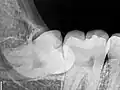

Рентгеновский снимок ретинированного нижнего правого зуба мудрости с горизонтальной ориентацией